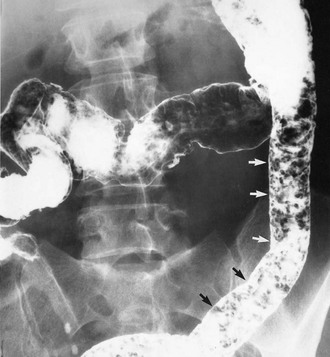

In longstanding colitis, the mucosa and submucosa undergo fibrosis, resulting in smoothing out of haustrations and a shortened colon which has a characteristic radiological appearance, the so-called lead pipe colon (Fig. 28.2).

Contrast radiology: If the clinical picture and histological findings are consistent with inflammatory bowel disease, the extent and degree of colonic involvement can be assessed by barium enema examination. Radiological appearances are illustrated in Figures 28.2 and 28.3. Contrast radiology is not usually performed in acute disease.